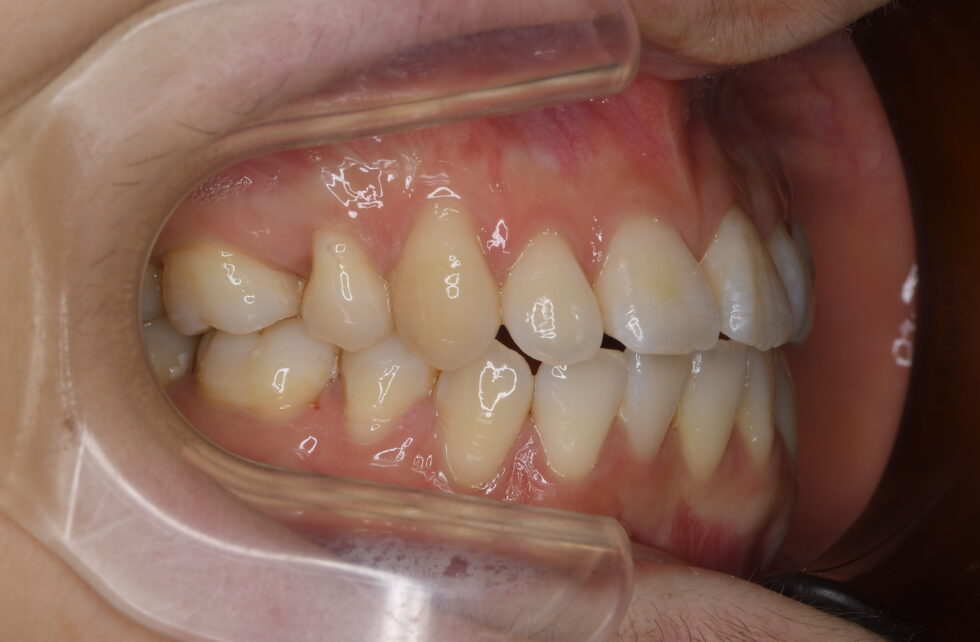

初診時年齢24歳の女性 上下顎前歯部叢生を主訴として来院された。数年前にも当院にご相談に来院されたが、中学生時で永久歯の抜歯に難色を示されたため見送ったとのことであった。

上顎左側側切歯が口蓋側転位となり右側第一大臼歯が口蓋側へ転位していた。下顎は左側中切歯、側切歯が唇舌的に重なり合っていた。叢生の状態に加え下顎が左側へ偏位して臼歯部は左下が内側へ極端に傾斜していた。上顎左右側第一小臼歯、下顎は正中のずれを補うように右側を第一小臼歯、左側は第二小臼歯を抜歯していただき上下顎舌側マルチブラケット装置を使用して動的治療を行った。臼歯部の頬舌的な傾斜を調整しながら咬合を適正化するのに時間を要した。仕事上、来院間隔が長くなる傾向があったため動的治療期間は3年5か月間を要した。 調整来院は27回であった。治療費の目安140万円程度